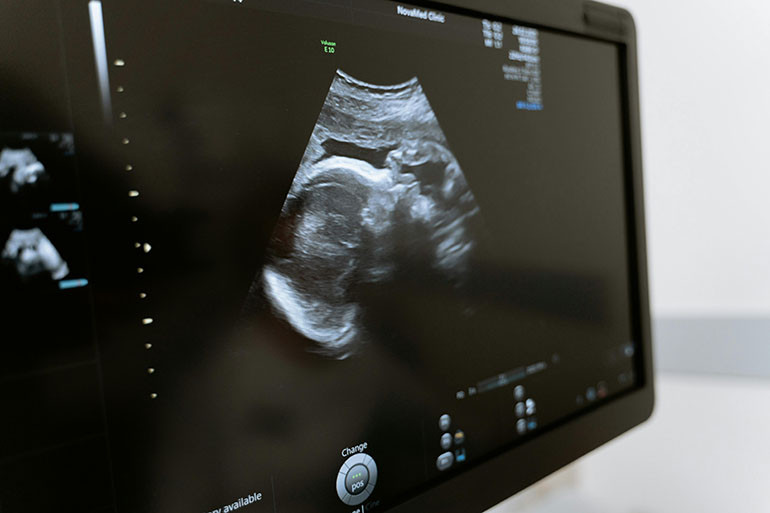

Ultrasound and other imaging services

At Planned Parenthood Zambia, we offer cutting-edge Ultrasound and Imaging Services to provide detailed insights into your health and support informed decision-making for personalized care. Our state-of-the-art facilities and skilled technicians ensure accurate and comprehensive imaging, empowering individuals to take control of their health journey.

• Ultrasound: High-resolution ultrasound imaging to visualize internal organs, monitor fetal development during pregnancy, and assess conditions such as ovarian cysts, uterine fibroids, and urinary tract issues.